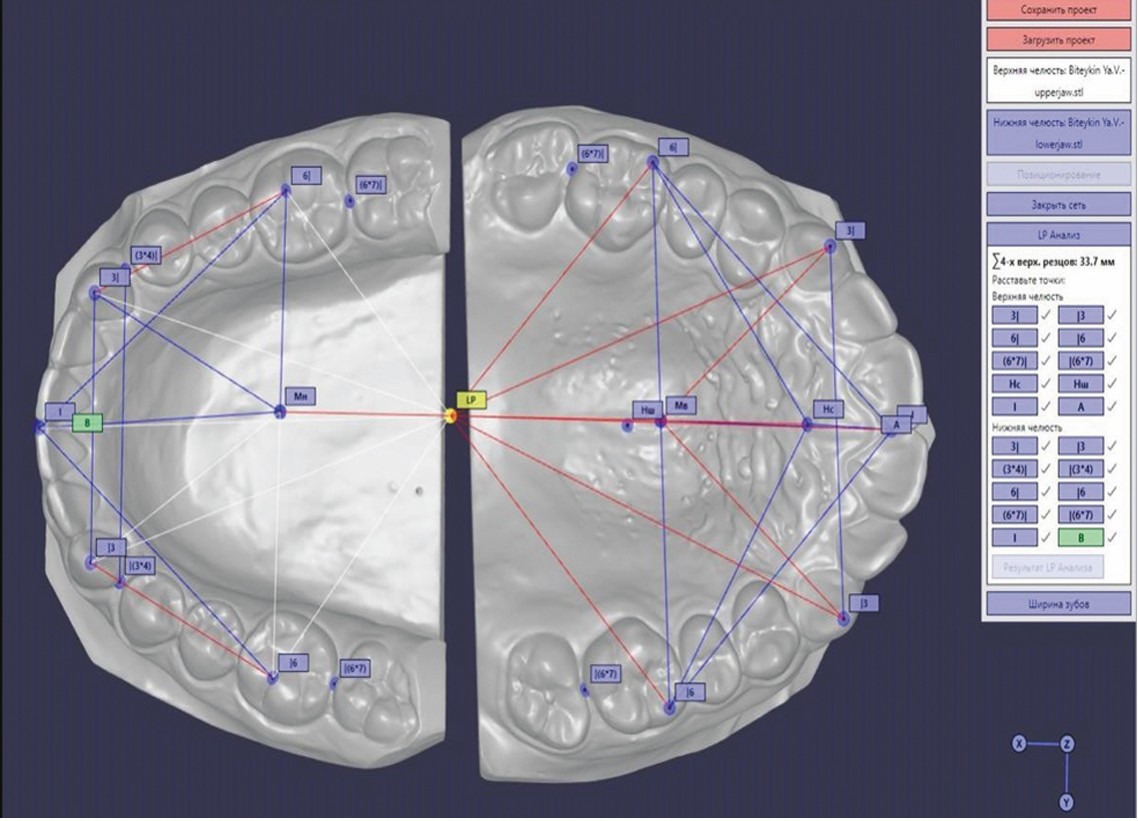

Нами был предложен новый подход для оценки положения зубов, зубных рядов, окклюзии относительно координатного параметра LP. Этот параметр определяется при пересечении линии N–Po, проходящей через точку N, расположенную на передне-верхнем крае носолобного шва, и точку Po, расположенную на вершине наружного слухового прохода, и окклюзионной линии, проходящей через срединную контактную точку на режущих краях центральных резцов и точку в области дистально-щечных бугров первых моляров (рисунок 4).

Рисунок 4. Определение координатного параметра LP.

Figure 4. Definition of the coordinate parameter LP.

Относительно точки LP проводится оценка положения первых моляров, клыков, резцов как верхнего, так и нижнего зубного ряда (рисунок 5).

Рисунок 5. Определение расстояний верхнего и нижнего зубного ряда от точки LP.

Figure 5. Determination of the distances of the upper and lower dental arches from the LP point.

Перед проведением данного анализа также измерялась сумма мезиодистальных размеров четырех резцов верхней челюсти. Такой метод оценки обеспечивает более глубокий анализ положения зубов, зубных рядов, а также их отклонений от нормальных значений, что в свою очередь повышает точность диагностики и улучшает планирование ортодонтического лечения.

В качестве примера приводится протокол диагностики положения зубов и зубных рядов относительно координатной точки LP (рисунок 6).

Рисунок 6. Протокол оценки положения зубов и зубных рядов относительно точки LP с использованием компьютерной программы при сумме 4 резцов верхней челюсти 29,0 мм.

Figure 6. Protocol for assessing the position of teeth and dental arches relative to LP point using computer software. The sum of the four upper incisors is 29,0 mm.